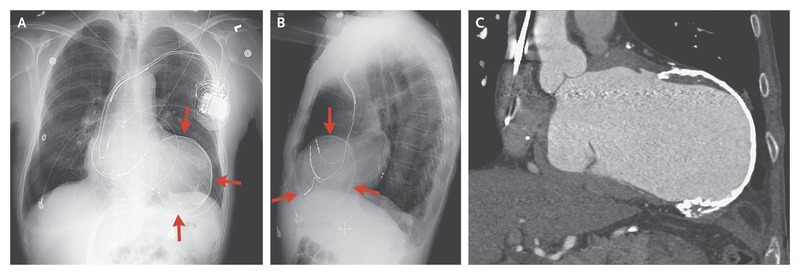

O aneurisma do ventrículo esquerdo é definido como uma porção do ventrículo que se torna fina e dilatada, com margens…